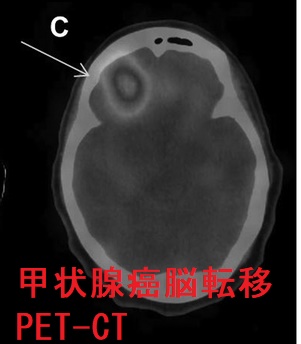

甲状腺癌分化癌(乳頭癌、濾胞癌)の脳転移は遠隔転移の約1%。脳神経症状・けいれんを起こし予後に大きく影響。単発性の場合は原発性脳腫瘍と鑑別できず、摘出後の病理標本で甲状腺乳頭癌・甲状腺癌濾胞癌の脳転移と分かる。最初から放射性ヨウ素(I-131)を取り込んでいれば放射線内・外照射、γナイフ、分子標的薬で治療。下垂体腫瘍で中枢性甲状腺機能低下症(非機能性下垂体腫瘍のほとんどが血清TSH基準値内)。ACTH産生腫瘍は中枢性甲状腺機能低下症を起こし易く、成長ホルモン(GH)産生腫瘍(先端巨大症)は起こし難い(いずれも約50%で血清TSH基準値内)。

甲状腺癌脳転移の診断は、

- FDG-PET/CT

脳転移は予後に大きく影響し、分化型甲状腺がん(乳頭癌・濾胞癌)患者における脳転移後の生存期間中央値は18カ月、1年生存率 63%、3年生存率 33%とされます[Clin Nucl Med. 2019 Jul;44(7):544-549.]。